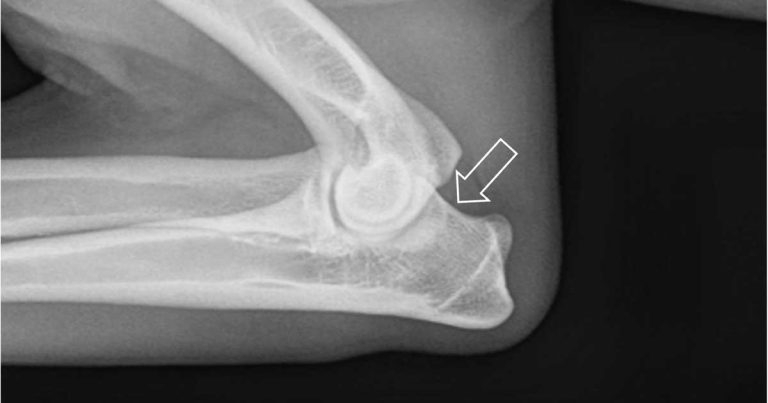

Ununited anconeal process is also an uncommon condition of medium-large breed dogs. The anonceal process should be fused by 16 weeks of age and the condition is best detected on a flexed mediolateral projection (Figure 5).